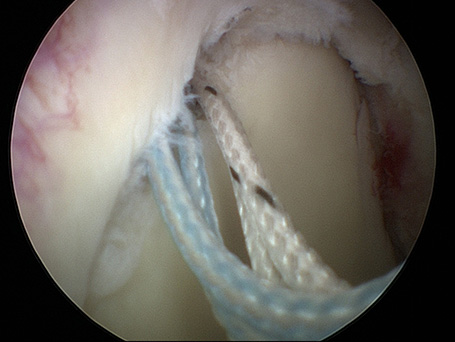

Neben der konservativen Behandlung bieten wir operativ sowohl arthroskopische als auch offene Stabilisationsoperationen an. Das Spektrum der operativen Behandlung reicht von reinen Kapselstabilisationsoperationen (Bankartrepair) über akute knöcherne Kapsellabrumabrisse bis hin zu veralteten komplexeren Instabilitätsoperationen mit Defektaufbau an der Schultergelenkspfanne bei fehlendem Knochen.

Durch die operative Behandlung wird dafür gesorgt, dass die verletzte Kapselstruktur an dem anatomischen Ort fixiert wird und so wieder anatomisch heilen kann. Die biologische Heilung muss im Rahmen der Nachbehandlung zuerst geschützt werden. Die Nachbehandlung der konservativen und operativen Kapsellabrumverletzungen unterscheidet sich daher prinzipell nicht wesentlich. Das Nachbehandlungsprogramm limitiert dementsprechend in den ersten 6 Wochen nach Operation das Bewegungsausmaß und die Aktivität. Ein Orthesenkissen begleitet regelmäßig diese Phase der Nachbehandlung. Somit sind insbesondere anfänglich auch die regelmäßigen, alltäglichen Verrichtungen und die Haushaltsführung eingeschränkt. Entsprechende Vorkehrungen sollten getroffen werden.

69-jähriger Patient mit linkseitiger Schulterluxationsverletzung. Bei älteren Patienten kommt es im Rahmen der Schulterverrenkungen häufiger zu Sehnenabrissen am Oberarmkopf. Trotz der Einrichtung des Gelenkes kann der Arm nicht wieder gut bewegt werden. Erst die operative, in diesem Falle rein arthroskopische Rekonstruktion der Sehnen und deren Einheilen ist eine Schultergelenksbewegung wieder gut möglich.